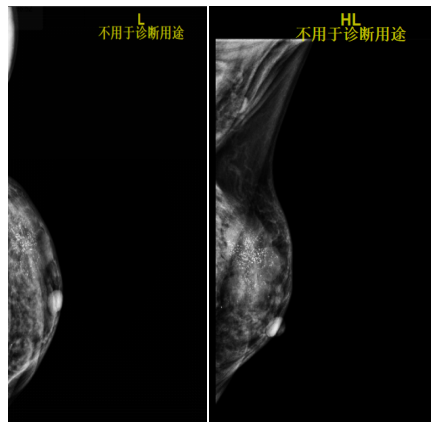

2021-6-9乳腺及腋窝淋巴结超声:左侧乳腺外上象限见大小约45*21mm低回声团块,边界不清,形态不规则,肿块前缘达皮肤层,内回声不均匀,内见多枚杂乱强光点,可见血流信号,测其动脉血流RI0.76。余双侧乳腺腺体形态、结构未见异常。左侧腋窝见多枚低回声结节,边界清,形态饱满,有包膜,内见多发强光点,较大者约13*10mm,内可见血流信号。右侧腋窝未见肿大淋巴结回声。

影像诊断:左侧乳腺低回声团块(BI-RADS:5类,考虑浸润性Ca);左侧腋窝多发异常肿大淋巴结。

图1.乳腺B超(2021-6-9)